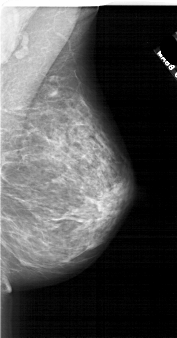

A_1744_1.LEFT_MLO

LEFT_MLO LINES 6721 PIXELS_PER_LINE 3376 BITS_PER_PIXEL 12 RESOLUTION 43.5 OVERLAY